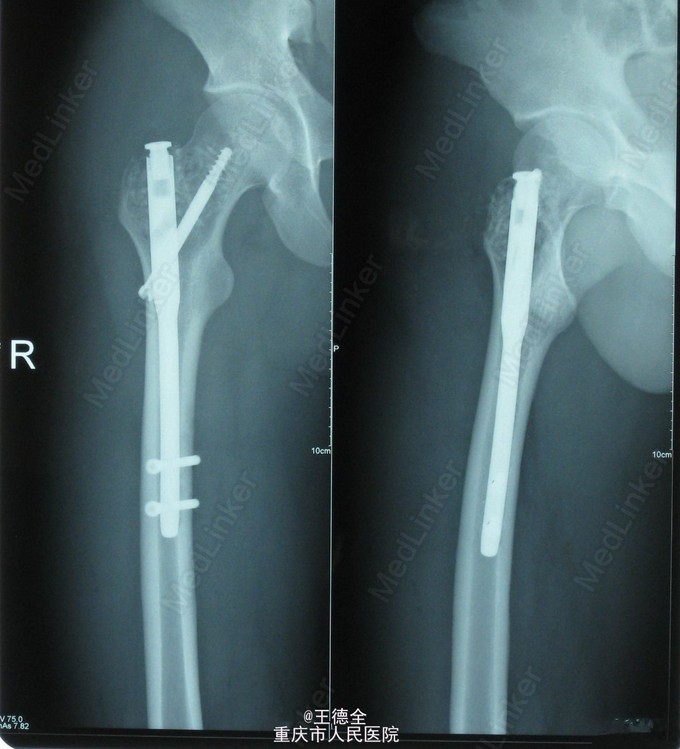

右股骨近端骨巨细胞瘤

患者男,21岁,因右髋部活动时疼痛3周入院,自诉既往无外伤史;查体:右髋部局部压痛,无红肿热痛,右髋关节活动可,右”4“字试验(+),右下肢肌力感觉正常。入院后完善相关检查,积极行病灶清除自体髂骨植骨伽马钉内固定术。